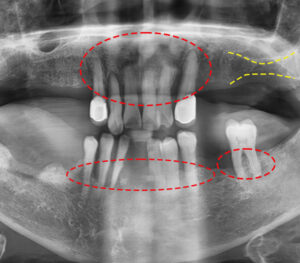

환자분께서는 남아있는 잔존 치아들이

치주질환과 염증으로 인해 잇몸뼈가

상당히 소실된 상태였으며 전체적인

치아 흔들림이 있는 상태로 내원해주셨습니다.

살릴 수 있는 치아가 없는 상태라 전악 발치를

진행하였으며 발치와 함께

염증 제거도 진행하였습니다.